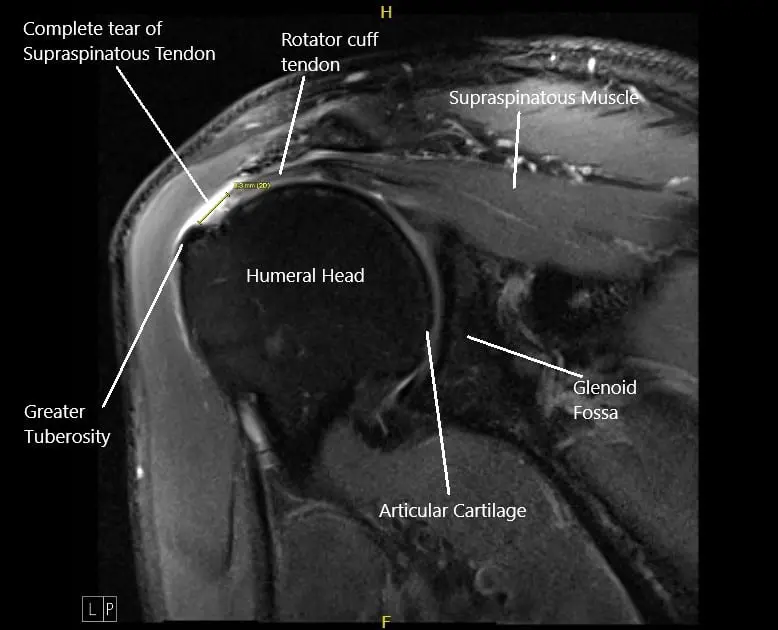

MRI image of the left shoulder showing a complete tear of the rotator cuff.

Radiological studies of the left shoulder suggested a complete tear of the supraspinatus tendon with 8 mm of medial retraction, infraspinatus, and long head biceps tendinosis, subacromial/subdeltoid, and subcoracoid bursitis, AC arthrosis, and degeneration of the superior posterior superior labrum.